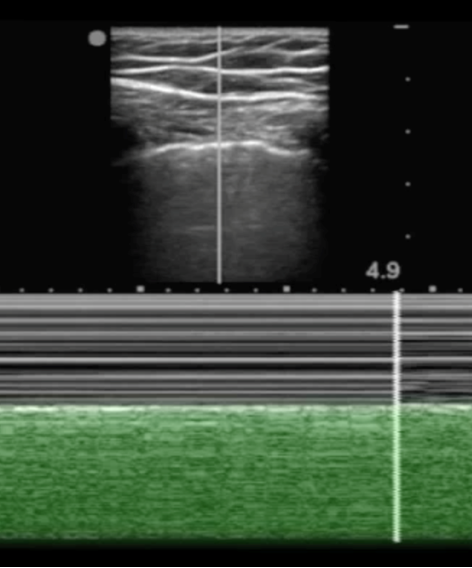

eFAST "Seashore Sign" Highlighted Image